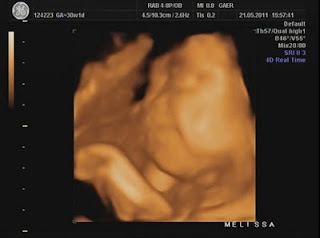

Hoje foi dia de análises e eco...

Durante a eco, percebi que a Dra ficou tempo a mais a avaliar o mesmo local e ao fim ela me explicou que viu uma lamina de água a volta do coraçãozinho da minha pricesa.

Ela me explicou que isso acontece a alguns bebés e que não devo me preocupar, que temos que fazer um exame mais detalhado para avaliar o coraçãozinho dela que será feito no Hospital São João e que hoje já trataria de marcar isso...